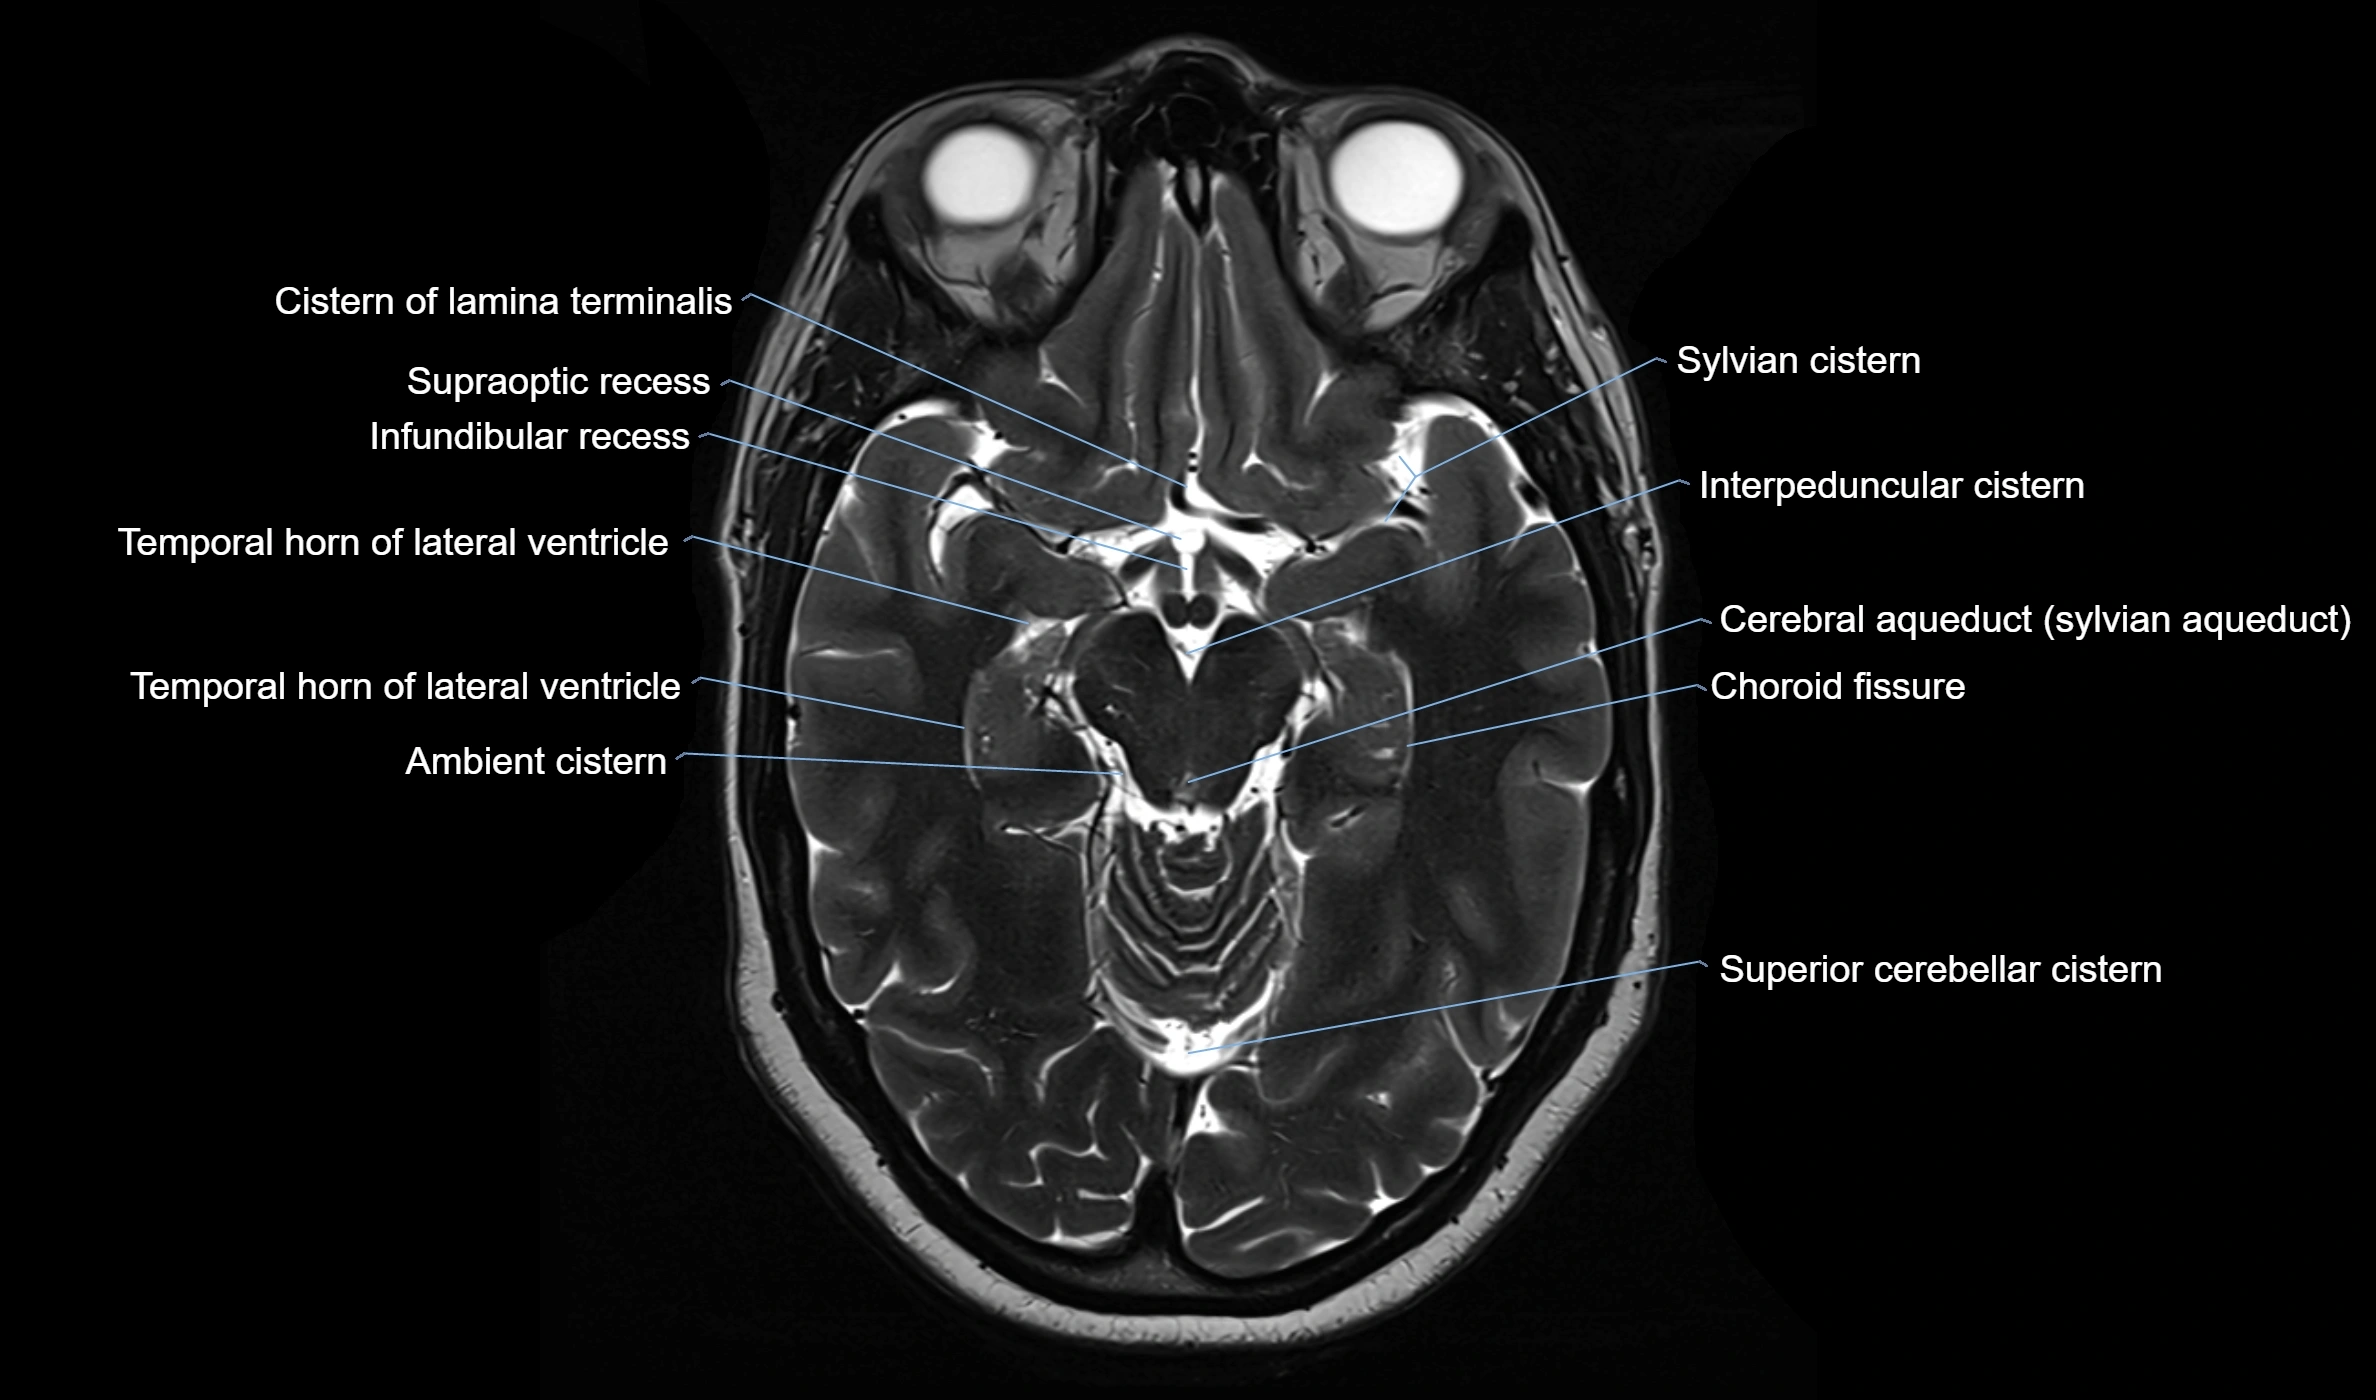

CT image

image